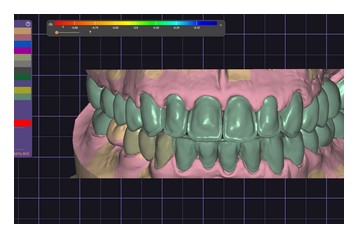

На этапе планирования комплексной реабилитации, было проведено интраоральное сканирование, фотопротокол, цифровая аксиография, данные которой использовались для последующей настройки виртуального артикулятора. Определено соотношение челюстей по нейромышечному протоколу с применением Миомонитора J5(TENS). По показаниям проведена репозиция нижней челюсти, в связи с чем была изготовлена каппа, фиксирующая терапевтическое исходное положение, так называемое Therapeutic Reference Position. То есть планирование имплантации проводилось уже не в исходном патологическом положении нижней челюсти, а в определенном терапевтическом, обеспечивая наиболее функционально выгодное расположение имплантатов относительно костного гребня. Позиционирование имплантатов на уровне 2.5, 2.6, 3.6, 4.6 - проводились под контролем хирургического шаблона.По завершению этапа остеоинтеграции и санации полости рта, приступили к этапу ортопедического лечения. В работе учитывались пожелания пациентки по эстетике. Объединив все полученные данные, мы приступили к построению зубных рядов с применением цифровых протоколов. В Программе Exocad был произведен расчет по индексу Шимбачи (LVI) ,что позволило определиться с оптимальной длиной фронтальной группы зубов, проведена моделировка Wax-up (Рис.8-9).

В связи с перестройкой окклюзии пациента, репозиции нижней челюсти применялся этап временного протезирования на коронках с опорой на собственные зубы и имплантаты, изготовленные по технологии CAD-CAM из PMMA (Рис.12-13).